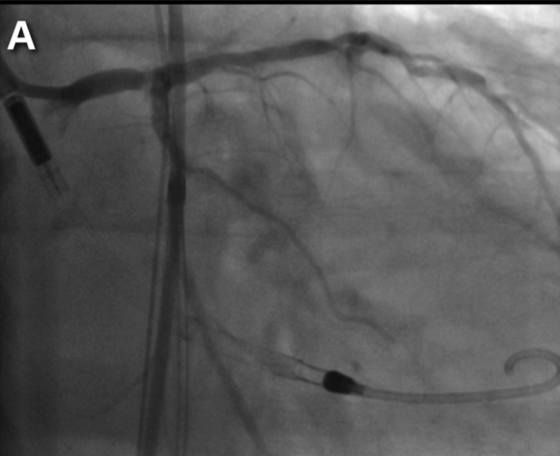

Protected PCI. The Impella 2.5 device was used in 18 of the 21 patients (85%), while an Impella CP was used in 3 patients (15%). Insertion of the Impella device was successful in all patients (100%) without the need for aortic valvuloplasty. All patients had severe left main stenosis; 2 patients (10%) had proximal left main stenosis and 19 patients (90%) had distal left main stenosis. Bifurcation stenting was performed with different techniques (5 with mini-crush technique, 1 with double-kissing crush technique, 11 with provisional technique, and 1 with V-stent technique). Two patients required rotational atherectomy due to severely calcified lesions (Figure 1).